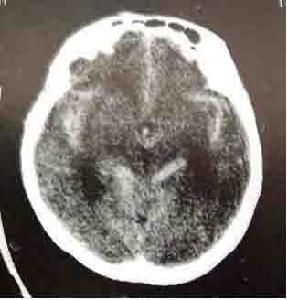

檢查

1.頭部CT診斷急性SAH準確,顯示腦溝與腦池密度增高。